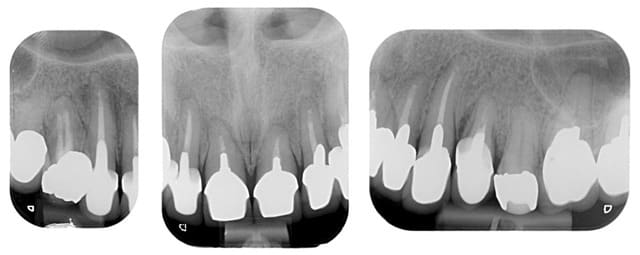

Une photo des préparations aurait été utile pour comprendre le choix des matériaux pour les CCM ou CCC.

> Une photo des préparations aurait été utile pour comprendre le choix des matériaux pour les CCM ou CCC.

> Notamment pour la 21 qui me semble un peu grise avec la provisoire sur l'angle

En ce qui concerne le choix entre ccc et ccm, il faut savoir que 90 % de mes couronnes sont en emax, mais dans le cas de racines extrêmement colorées ( ce qui est le cas ici)mon choix se porte sur des ccm classiques pour masquer ces colorations radiculaires que même une chape opaque sur emax ne peux dissimuler aussi bien qu'une ccm.